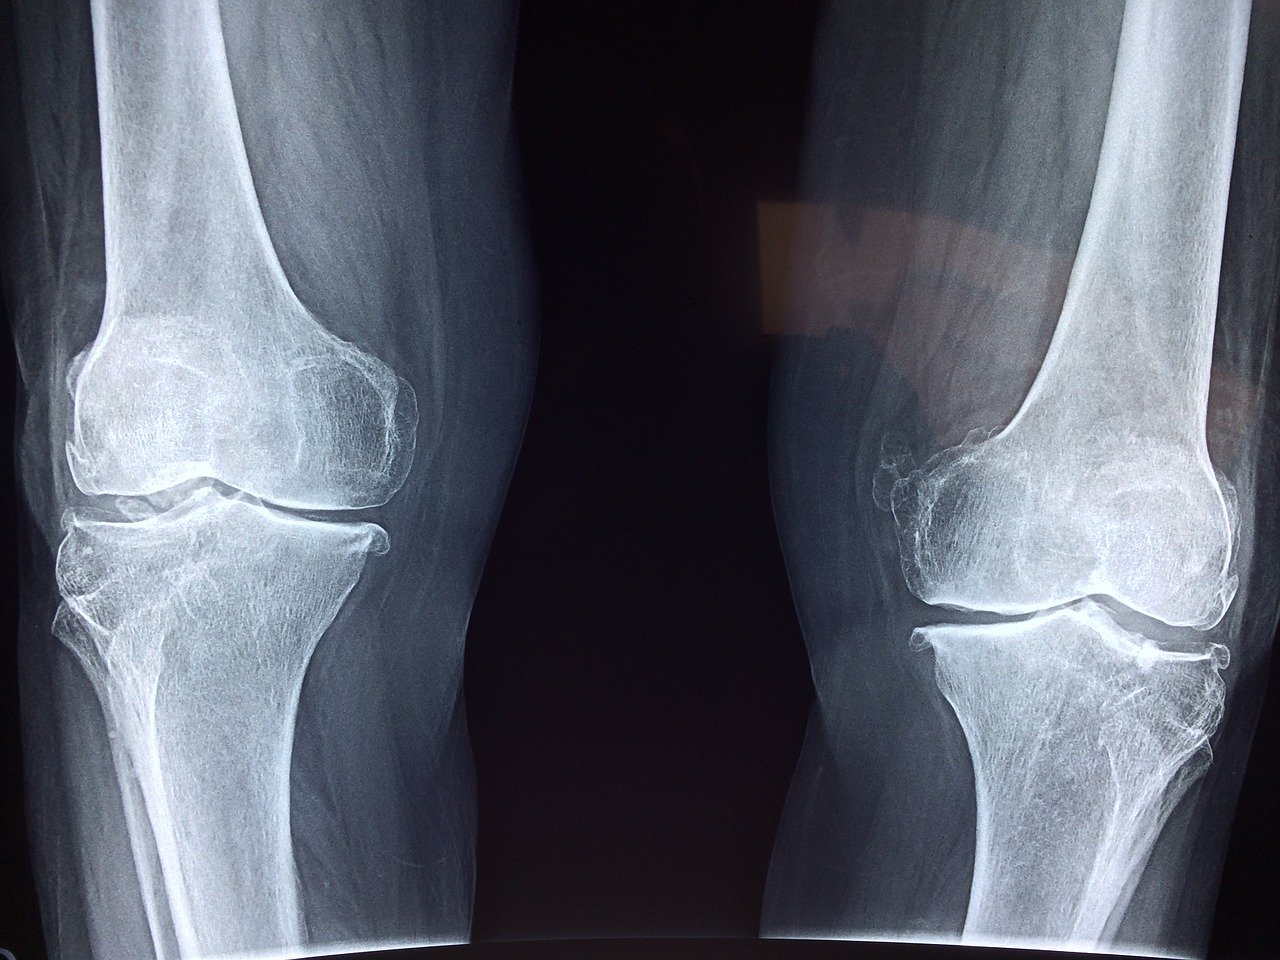

Wyróżnia się różne bóle kolana, a ich intensywność, nasilenie czy rodzaj jest zależny od przyczyny. Okazuje się, że staw kolanowy każdego dnia narażony jest na liczne dysfunkcje. Samo kolano może boleć nie tylko w wyniku stłuczenia, nagłego urazu czy sportowej kontuzji. Bardzo często wynika z pojawienia się stanu zapalnego w stawie kolanowym, bądź stanu zwyrodnieniowego. Na bolesność kolan narażeni są też seniorzy oraz osoby borykające się z otyłością.

Niwelowanie bólu kolan zależy od tego, dlaczego taka dysfunkcja w ogóle występuje. Właśnie dlatego do lekarza powinniśmy udać się już na początku pojawienia się dolegliwości bólowych, zanim zapalenie stawu kolanowego, zwyrodnienie czy inna choroba w jego obrębie się rozwinie. W przypadku stłuczeń czy pęknięć ból może być tak silny, że uniemożliwi normalne funkcjonowanie.